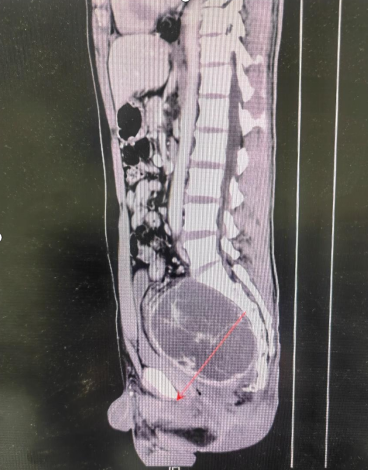

37岁的李先生近年来被反复出现的下腹坠胀、排尿困难等问题困扰,生活质量严重下降。经检查发现,其盆腔内存在一巨大占位性病变,进一步诊断明确为盆腔巨大肿瘤。肿瘤直径接近20厘米,几乎填满了整个盆腔,与直肠、膀胱、输尿管及重要血管神经关系密切。

面对这一复杂病例,医护团队迎难而上。为确保手术安全、提高治疗效果,科室启动了多学科诊疗(MDT)模式,联合放射科、泌尿外科、血管外科、麻醉科、手术室、输血科等多个科室专家进行深入讨论。团队通过高分辨率影像资料对肿瘤的形态、血供、与周围脏器的关系进行了三维重建与细致评估,制定了周密的手术方案和应急预案。同时,医护团队为患者进行了充分的肠道准备、备血等术前工作,为打赢这场“硬仗”做足了准备。

手术当天,由张翼主刀,高凯、郭一航密切配合,手术如期进行。正如术前预料,手术过程“险象环生”。肿瘤组织质地柔软,血运极其丰富,像一张致密的网,与盆壁、直肠、膀胱、精囊腺及髂血管等紧密粘连,分离过程中极易引发难以控制的大出血。手术团队临危不乱,凭借丰富的经验和精湛的技术,在方寸之地的盆腔内进行精细解剖与操作。他们小心翼翼地分离粘连,一丝不苟地结扎血管,稳扎稳打地推进手术进程。麻醉团队全程保驾护航,严密监测患者生命体征;输血科保障了血液制品的及时供应。

经过近10个小时的连续奋战,团队最终将这一巨大的肿瘤完整切除,未损伤直肠、膀胱等重要脏器,最大程度保护了患者的神经功能和排尿、排便控制能力以及性功能。手术共输注红细胞1600毫升、血浆450毫升,患者生命体征始终保持平稳。